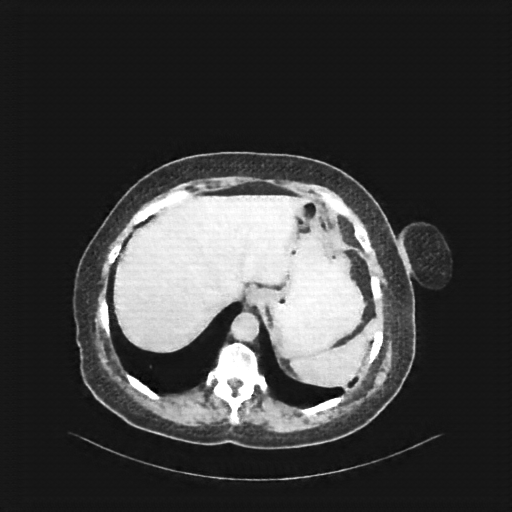

Original NATIVE CT scan (input)

Full window (WL 1023.5, WW 4095 β Low β1024, High +3071)

Actual HU range: [-160.0, 240.0]